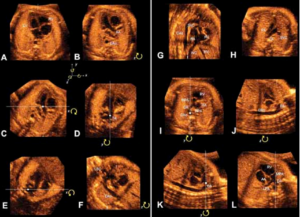

Στο κέντρο μας διενεργείται ο πλήρης υπερηχογραφικός έλεγχος που μπορεί να απαιτηθεί κατά τη διάρκεια της κύησης καθώς και επεμβατικός έλεγχος με βιοψία χοριακών λαχνών και αμνιοπαρακέντηση.

Όλες οι υπερηχογραφικές και επεμβατικές εξετάσεις πραγματοποιούνται σε ένα φιλικό και ήρεμο περιβάλλον με εξοπλισμό τελευταίας τεχνολογίας.